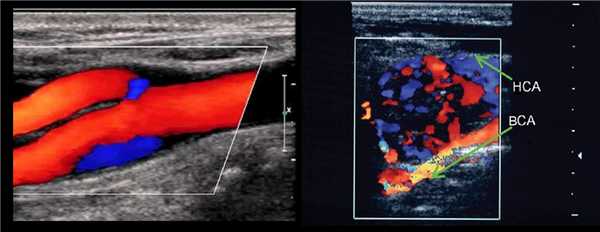

В В-режиме и ЦДК сканируют ОСА до бифуркации; выше бифуркации исследуют НСА через передний доступ, ВСА через боковой доступ.

В луковице ламинарный поток по основной оси ВСА красный, а зона турбулентного потока у наружной стенки окрашивается в синий.

ЦДК — эффективный вспомогательный методом для подтверждения проходимости вены.

Весь широкий просвет вены должен полностью обозначатся цветом.